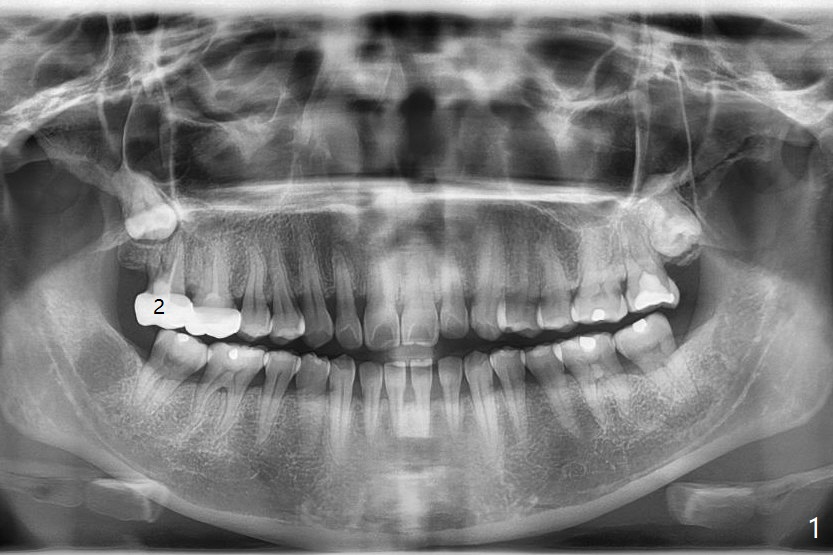

A 38-year-old woman returns to clinic with severe pain in the upper right 2nd molar (Fig.1), requesting immediate extraction. Endo consultation confirms nonsalvageability with gutta percha sticking out of the distobuccal root (Fig.2 arrowheads (B: buccal)). She would like to have an implant. What is the treatment plan? In fact the tooth #2 has been extracted with socket preservation.

The tooth #1 should have been extracted buccodistally (Fig.3,4). Three or 4 months later, a 5x10 mm implant could be placed distopalatally superiorly to avoid removing the tooth #1 with ~ 1.5 mm clearance (Fig.5). To place an implant in orthopedic manner, the tooth #1 will be removed, while the implant should be longer (5x13 mm) to engage the bone superior to the socket of the tooth #1 (Fig.6).

The socket of #2 heals 13 days postop; it appears that the bone graft remains in place (Fig.7,8 *). The patient is instructed to return in 3-4 months for impression and CT for guide. The socket heals 4 months postop (Fig.9,10). She plans to have implant next year, since she wants to add another insurance. The patient returns for implant without removal of the third molar 2 years 4 months post socket preservation (Fig.11). A 5x7.3 mm implant can be placed without invading the sac of the impacted third molar (Fig.12). In fact the lab has a better plan. A lump of bone forms in the previous socket 1 year 4 months postop (Fig.13 *). The ridge is wide and dense (Fig.14). A narrow implant placed oblique could be longer (Fig.15), as compared to a wide, short one (Fig.12).